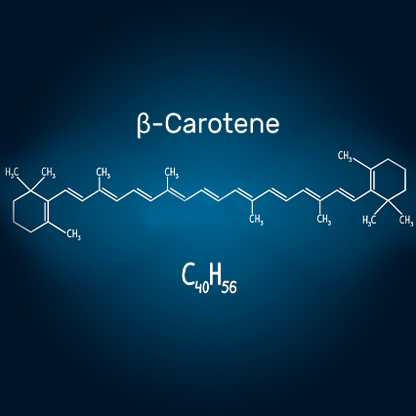

Kapsule s beta-karotenom za vid

Sastojci u preparatu O caps ojačavaju cilijarni mišić koji kontroliše kristalno sočivo i štiti ga od pretjeranog naprezanja

Preporučili oftalmolozi O caps

"Pogoršanje vida je problem za ljude koji mnogo čitaju ili rade za računarom. Naočare i kontaktna sočiva pogoršavaju situaciju još i više jer oči slabe i ne možete dobro da vidite bez pomoći. Laserska operacija oka takođe nije opcija. Ako se ne riješite uzroka pogoršanja vida (računara, TV-a, pametnih telefona), efekat operacije će da traje samo 1-2 godine. Možete popraviti vid pomoću dodatka s ekstraktom borovnice - O caps. Tajna ovih je ispravna doza sastojaka, namještena tako da izoštri vid i poboljša jasnoću bez obzira na veliki napor."